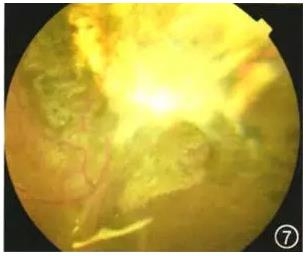

眼科检查:视力:右眼0.02,左眼1.0,眼压:右眼10 mmHg(1 mmHg=O.133 kPa),左眼14 mmHg,右眼前节未见明显异常,玻璃体混浊,视乳头鼻上方可见一蘑菇样粉红色肿物,无色素,表面光滑,可见血管爬行,黄斑区中心凹反光不清(图1)。左眼未见明显异常。

图1 右眼视力下降患者右眼彩色眼底照相

出院后患者规律门诊复查,于2015年11月23日行右眼硅油取出术。术后随访:右眼视力30 cm指数,眼压:10 mmHg,角膜透明,角膜后沉积物(+),前房深,房水闪光(+),虹膜6点位根切口畅,瞳孔圆,晶状体缺如,玻璃体腔少许乳化油滴,眼底视网膜平伏,可见鼻上方大片白色瘢痕,未见肿瘤复发(图7)。

图7 右眼脉络膜平滑肌瘤患者晶状体玻璃体切除+眼内肿瘤切除+视网膜切开+眼内光凝+注药+重水+硅油填充术后10个月右眼彩色眼底照相